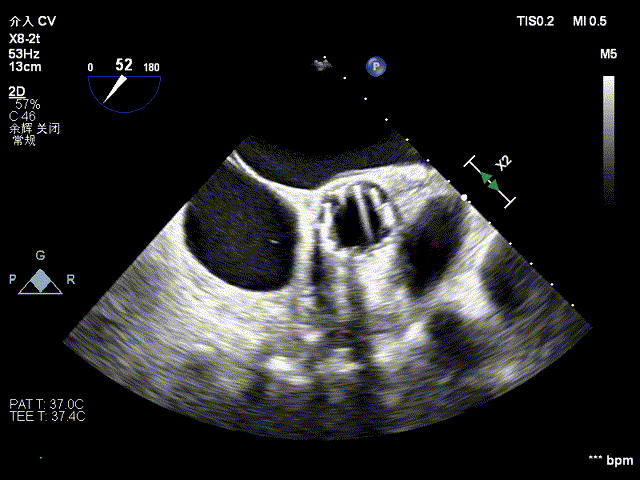

术前食道超声

术后食道超声

术后心脏超声示

经心尖主动脉瓣生物瓣置换术后,生物瓣功能未见明显异常,微量心包积液。LVEF:68%。

主动脉瓣位生物瓣,瓣架固定,瓣叶启闭尚可,主动脉瓣位生物瓣前向峰值流速约1.8m/s,平均跨瓣压差约8mmHg,舒张期少量周反流。